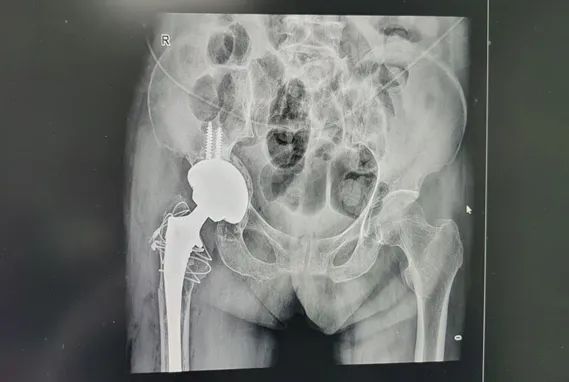

针对刘奶奶的具体情况,经过详细的病情讨论、检验与影像学检查,确诊其为右髋关节置换术后假体松动,需行右全髋关节翻修术,并为此制定了个性化的手术方案及应对措施。

全髋关节假体翻修术对手术医生的技术水平、手术团队的配合以及医院的硬件设施都有着极高的要求。手术过程中,尹绍猛教授凭借丰富的临床经验和精湛的手术技巧,克服了重重困难,成功为刘奶奶完成了右全髋关节翻修术。术后,刘奶奶恢复良好,疼痛明显缓解,关节功能也得到了显著改善,术后第二天已在康复师的指导下下床站立。刘奶奶及家属对尹绍猛教授及骨科团队的精湛医术和优质服务表示衷心的感谢。

与初次髋关节置换相比,髋关节翻修手术面临更多挑战,如假体取出、骨缺损重建、假体选择及固定方法等。大多数髋关节翻修病例都存在不同程度的骨缺损,而充足的骨支撑是假体获得初始稳定性及远期疗效的基础,因此骨缺损的重建直接关系到手术成败。术前需结合X线片、三维CT等影像学资料,仔细评估骨缺损程度并制定植骨方案。骨缺损修复后,还需选择适宜的假体及固定方式以完成关节功能重建。